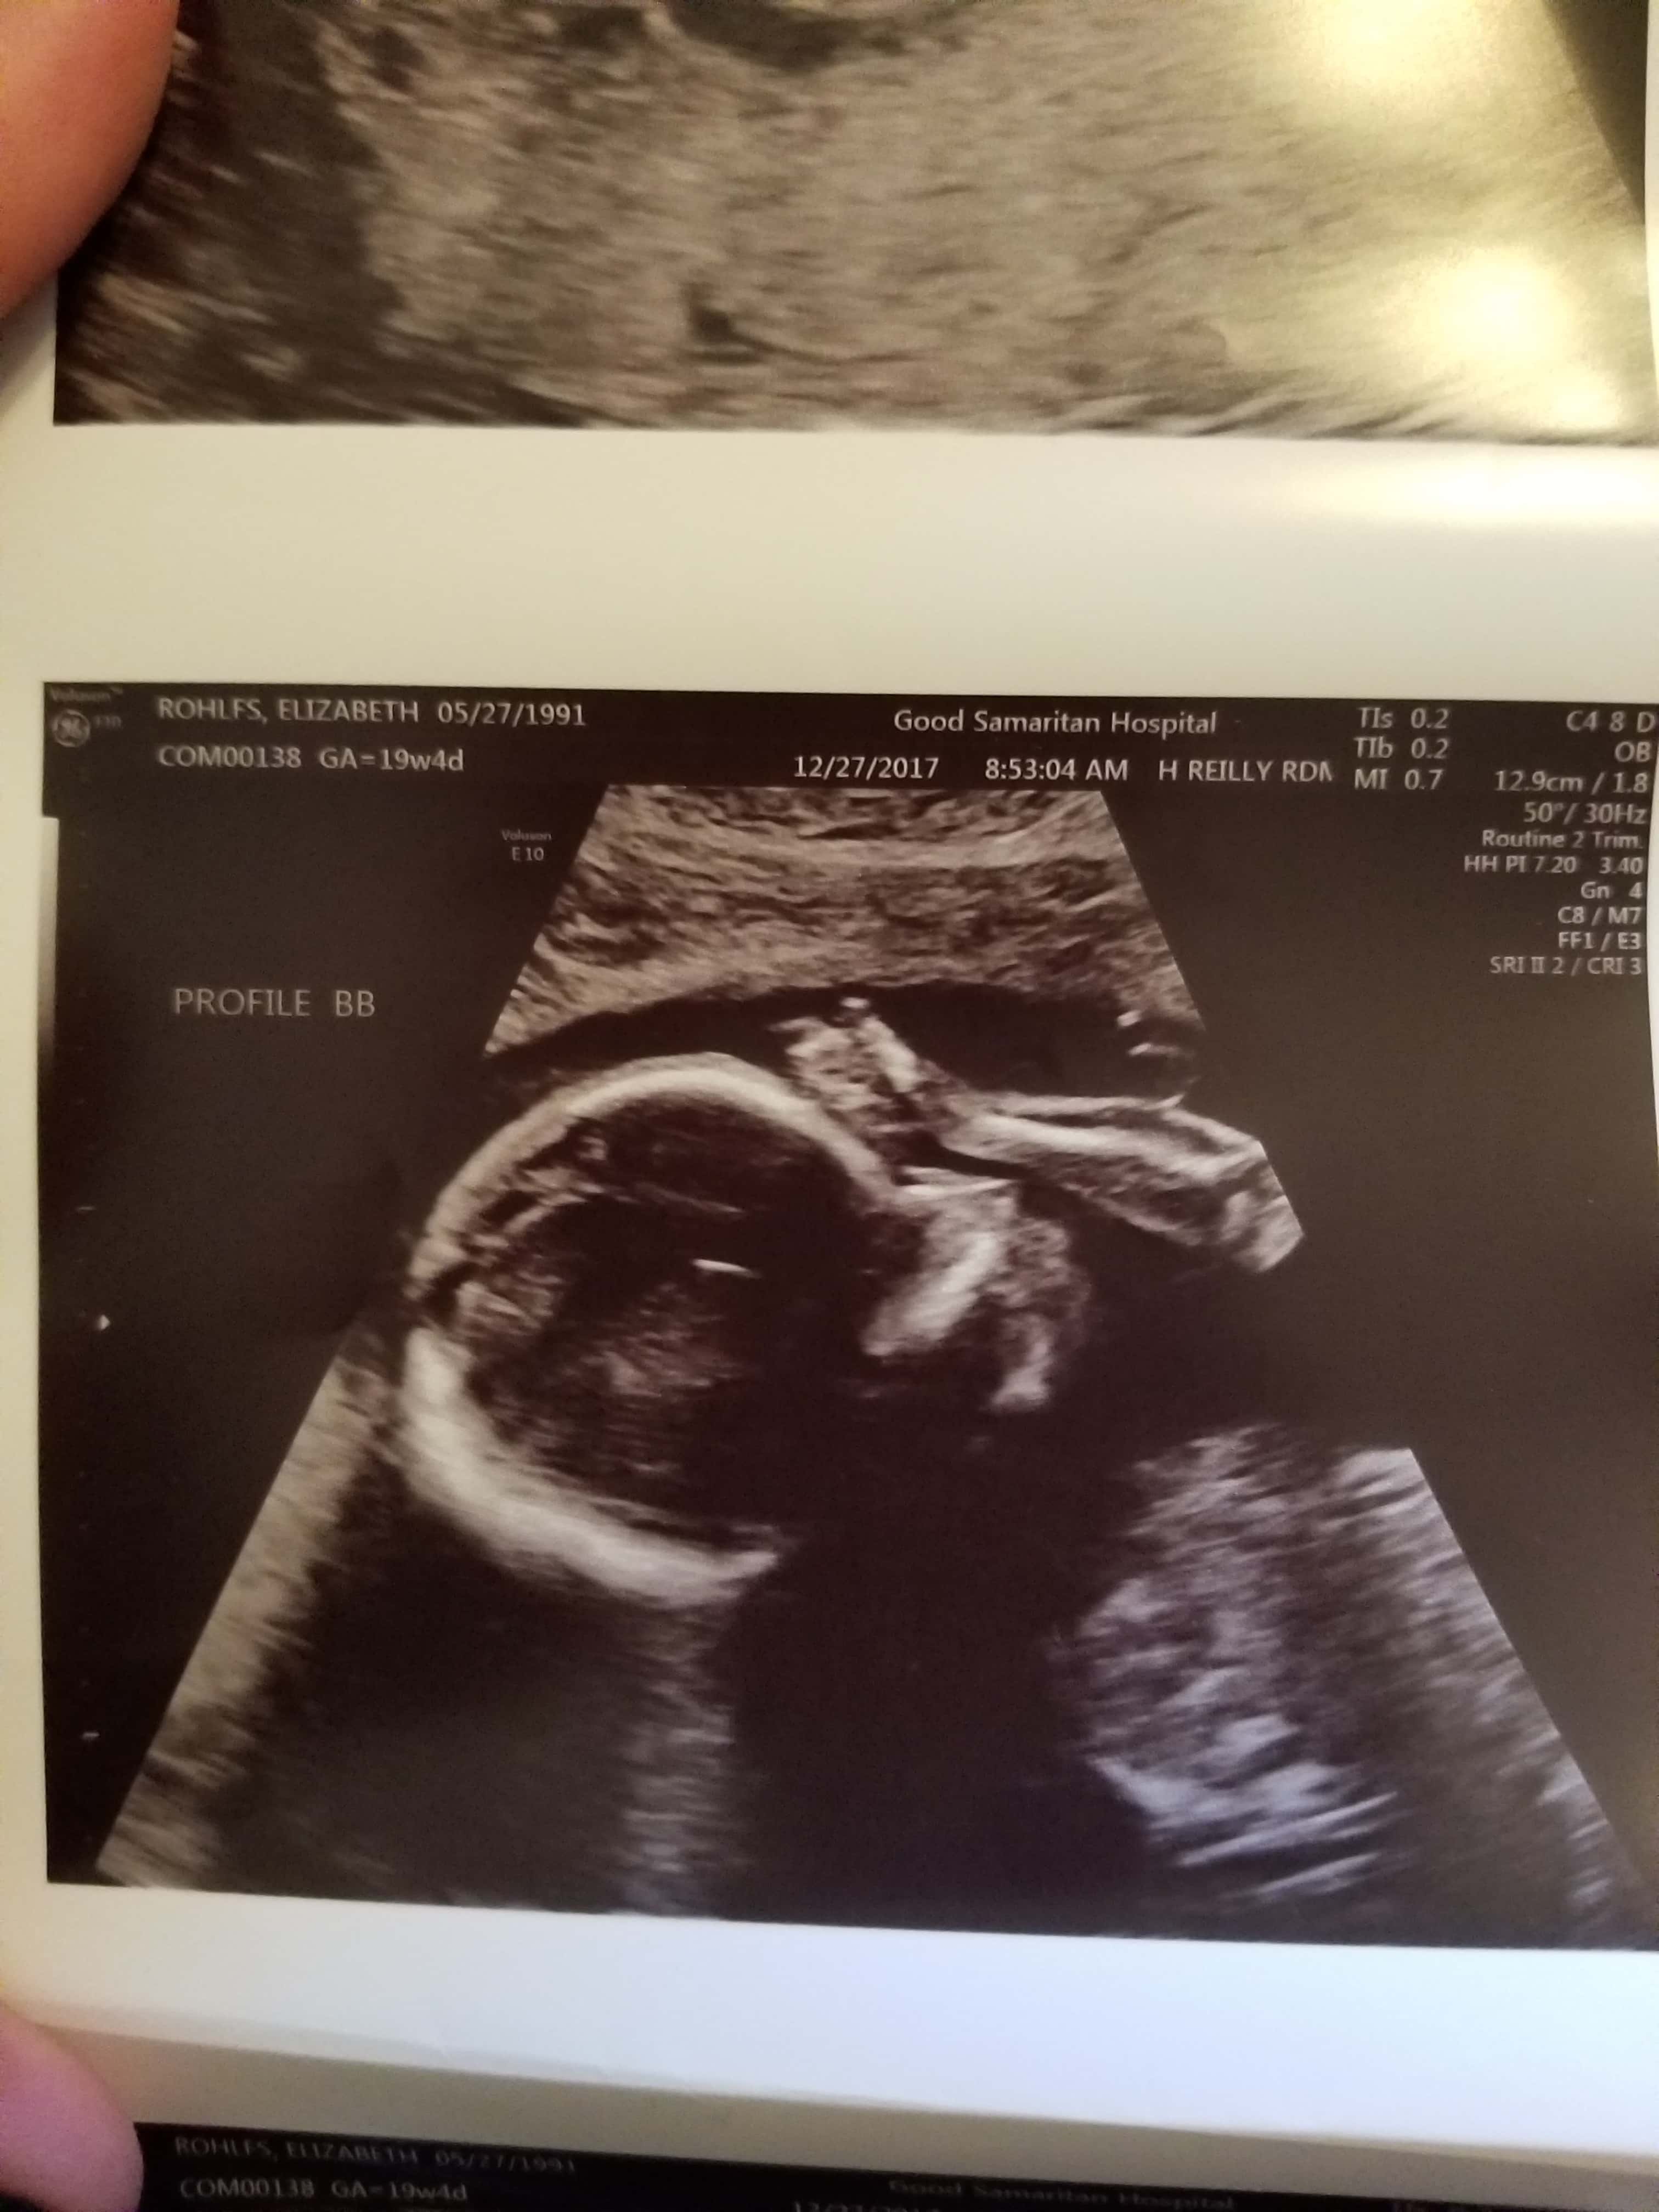

Ultrasound Photos at 19 Weeks Pregnant With Twins